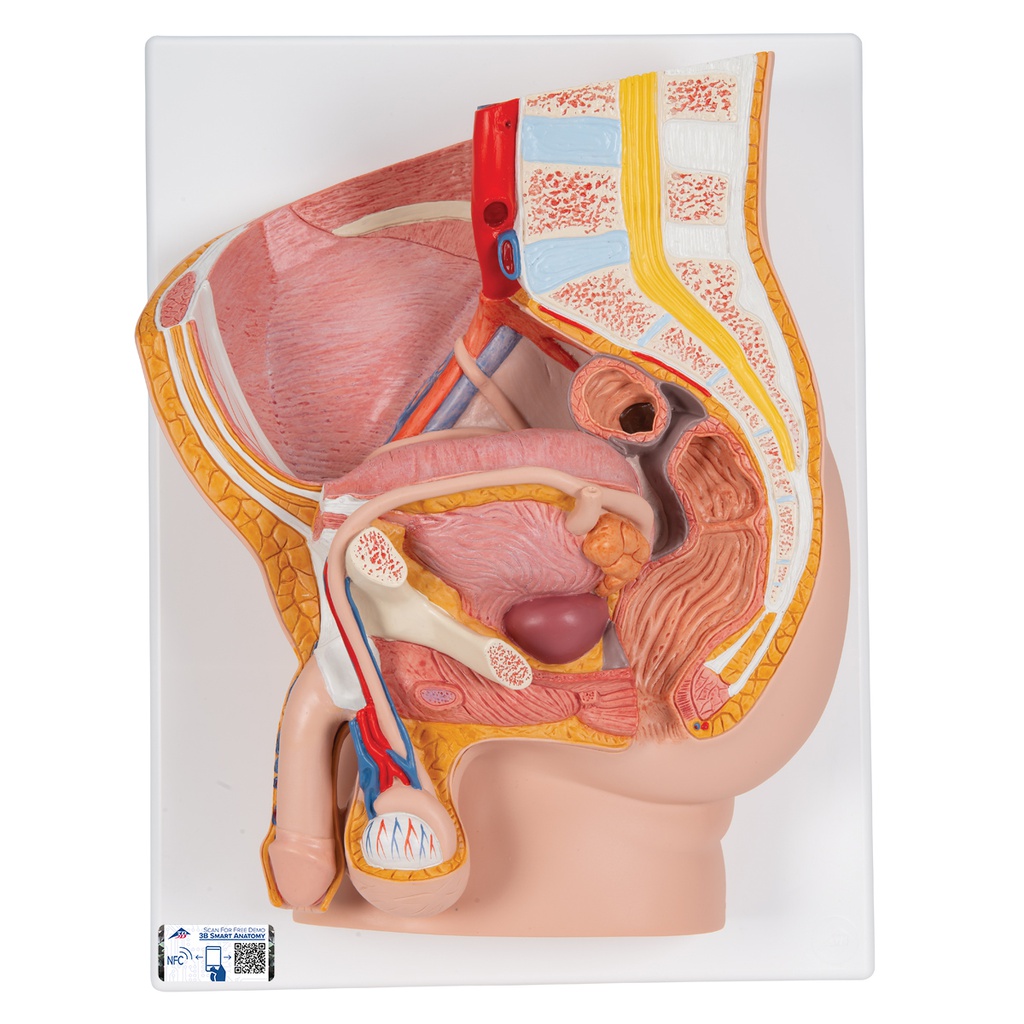

Male pelvis model in median section, 2 part

The male pelvis anatomy model is shown in median section. One half of male genital organs with bladder is shown at the normal position in the male pelvis. The rectum is removable for a more detailed study of the male pelvic anatomy. This high quality anatomy model is delivered on baseboard offering the possibility to be mounted to the wall.